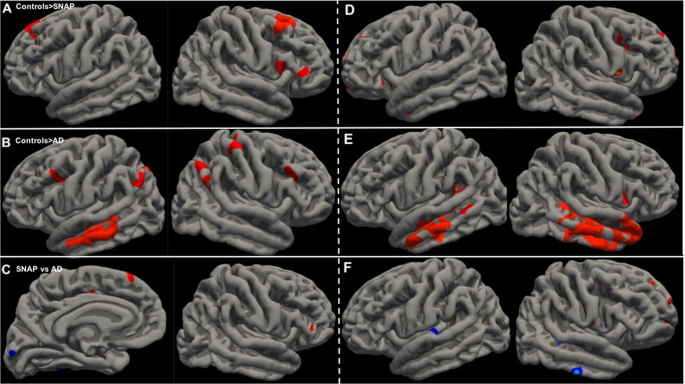

The vertexwise comparison of cortical thickness between patients and controls showed a significant decrease in the frontal lobes (superior and middle frontal gyri) in SNAP patients and in the temporo-parietal and frontal lobes in AD patients. The direct comparison between SNAP and AD patients showed lower (uncorrected) baseline cortical thickness in the frontal cortex in SNAP patients and in the posterior (temporal and occipital) cortex in AD patients (Fig. 3).

Vertexwise comparison of baseline cortical thickness controlled for age showed lower thickness in: A SNAP patients compared with controls (clusterwise correction for multiple comparisons, p < 0.05); B AD patients compared with controls (clusterwise correction for multiple comparisons, p < 0.05); and C SNAP patients (in red) and AD patients (in blue) when compared to each other (medial view of the left hemisphere and lateral view of the right hemisphere, p < 0.001, uncorrected). Vertexwise comparison of the symmetrized percent change of cortical thickness controlled for age after 2 years showed a higher decrease in: D SNAP patients vs controls (p < 0.001, uncorrected); E AD patients vs controls (clusterwise correction for multiple comparisons, p < 0.05); and F SNAP patients (in red) and AD patients (in blue) when compared to each other (clusterwise correction for multiple comparisons, p < 0.05 in the left hemisphere, and p < 0.001, uncorrected in the right hemisphere).

The vertexwise comparison of the symmetrized percent change of cortical thickness after 2 years showed a significant decrease in the temporal lobes for AD patients compared with controls (n = 28). The (uncorrected) comparison between SNAP patients and controls showed spots of decreased cortical thickness in the frontal lobes. The comparison between AD and SNAP patients showed a cluster of decreased cortical thickness in the left superior temporal gyrus in AD patients and (uncorrected) spots in the frontal lobes in SNAP patients (Fig. 3).